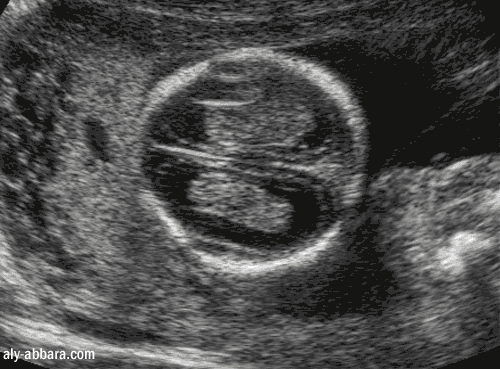

Cerveau fœtal normal à 16 SA : coupe coronale passant par

les ventricules latéraux occupés par les plexus choroïdes